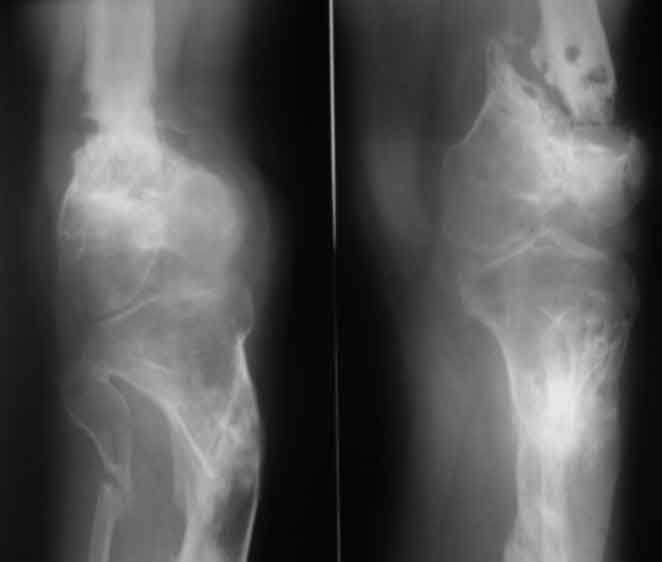

Псевдоартроз дистального отдела бедра. Distal femur nonunion

Псевдоартроз дистального отдела бедра. Distal femur nonunion у пациента 26 лет

Открытый перелом н/3 бедра и в/3 голени в 2006 году. выполнен малоинвазивный накостный остеосинтез после заживления ран (снимки утеряны), через 3 мес после остеосинтеза - глубокое нагноение, консультировался и лечился с 2006 года в одном из лучших НИИ. многократные остеотомии, компрессии, дистракции. В августе 2010 - снят аппарат в поликлинике в центре, рекомендации - ходить в ортезе, показаться через 2 мес, консультирован в другом НИИ - рекомендовано дообследование (приличный список, каждый раз добавлено нечто новое).

В итоге попал к нам, движения в к/с отсутствуют, подвижность только на уровне ложняка, передненаружная поверхность области к/с представляет собой многочисленные рубцы от доступов, закрытых свищевых ходов. Свищей нет на протяжении 3 лет, кровь не воспалительная, СРБ - отс.

Коленный сустав не работает и вряд ли заработает, ось голени нарушена, дистальный фрагмент бедра очень короткий. Если думать о восстановлении опороспособности ноги, то, мне кажется, только совместив интрамедуллярный остеосинтез длинным гвоздем трансартикулярно с артродезом коленного сустава и коррегирующей остеотомией большеберцовой (и малой берцовой) кости.

На фото R-гр к сожелению не захвачена вся голень. На самом деле там не просто деформация, а еще запаянный канал. Не на ограниченном участке, а практически на всем протяжении. Формирование канала, даже известными способами может превратиться в неконтролируемое разрушение большеберцовой кости. Вот и думаем, может ограничиться фиксацией проксимального метафиза большеберцовой, до деформации.